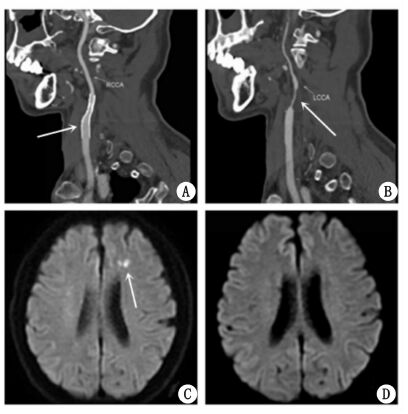

CAS术后1个月,患者因突发右侧肢体无力再次急诊就诊本院。入院查体显示患者右上肢肌力Ⅱ级,右下肢肌力Ⅲ级,左侧肢体肌力较前次住院无明显变化。复查颈动脉CTA显示原右侧颈内动脉支架位置良好,管腔通畅(图 2A)。左侧颈内动脉再通,管腔呈重度狭窄,狭窄率约90%(图 2B)。而头颅磁共振显示左侧额叶多发新鲜梗死灶(图 2C)。结合影像学检查结果,笔者认为患者左侧急性脑梗死为左颈内动脉自发性再通引起斑块脱落所致,建议患者1个月后行左颈内动脉支架植入术,但患者拒绝。故患者病情稳定后出院,继续药物保守治疗。目前患者随访16个月,未再发脑卒中及TIA。

图 2 患者颈动脉支架植入术后复查颈动脉CTA(A、B),术后头颅MRI弥散加权图像(DWI)(C),术前同一患者头颅MRI弥散加权图像(DWI)(D)